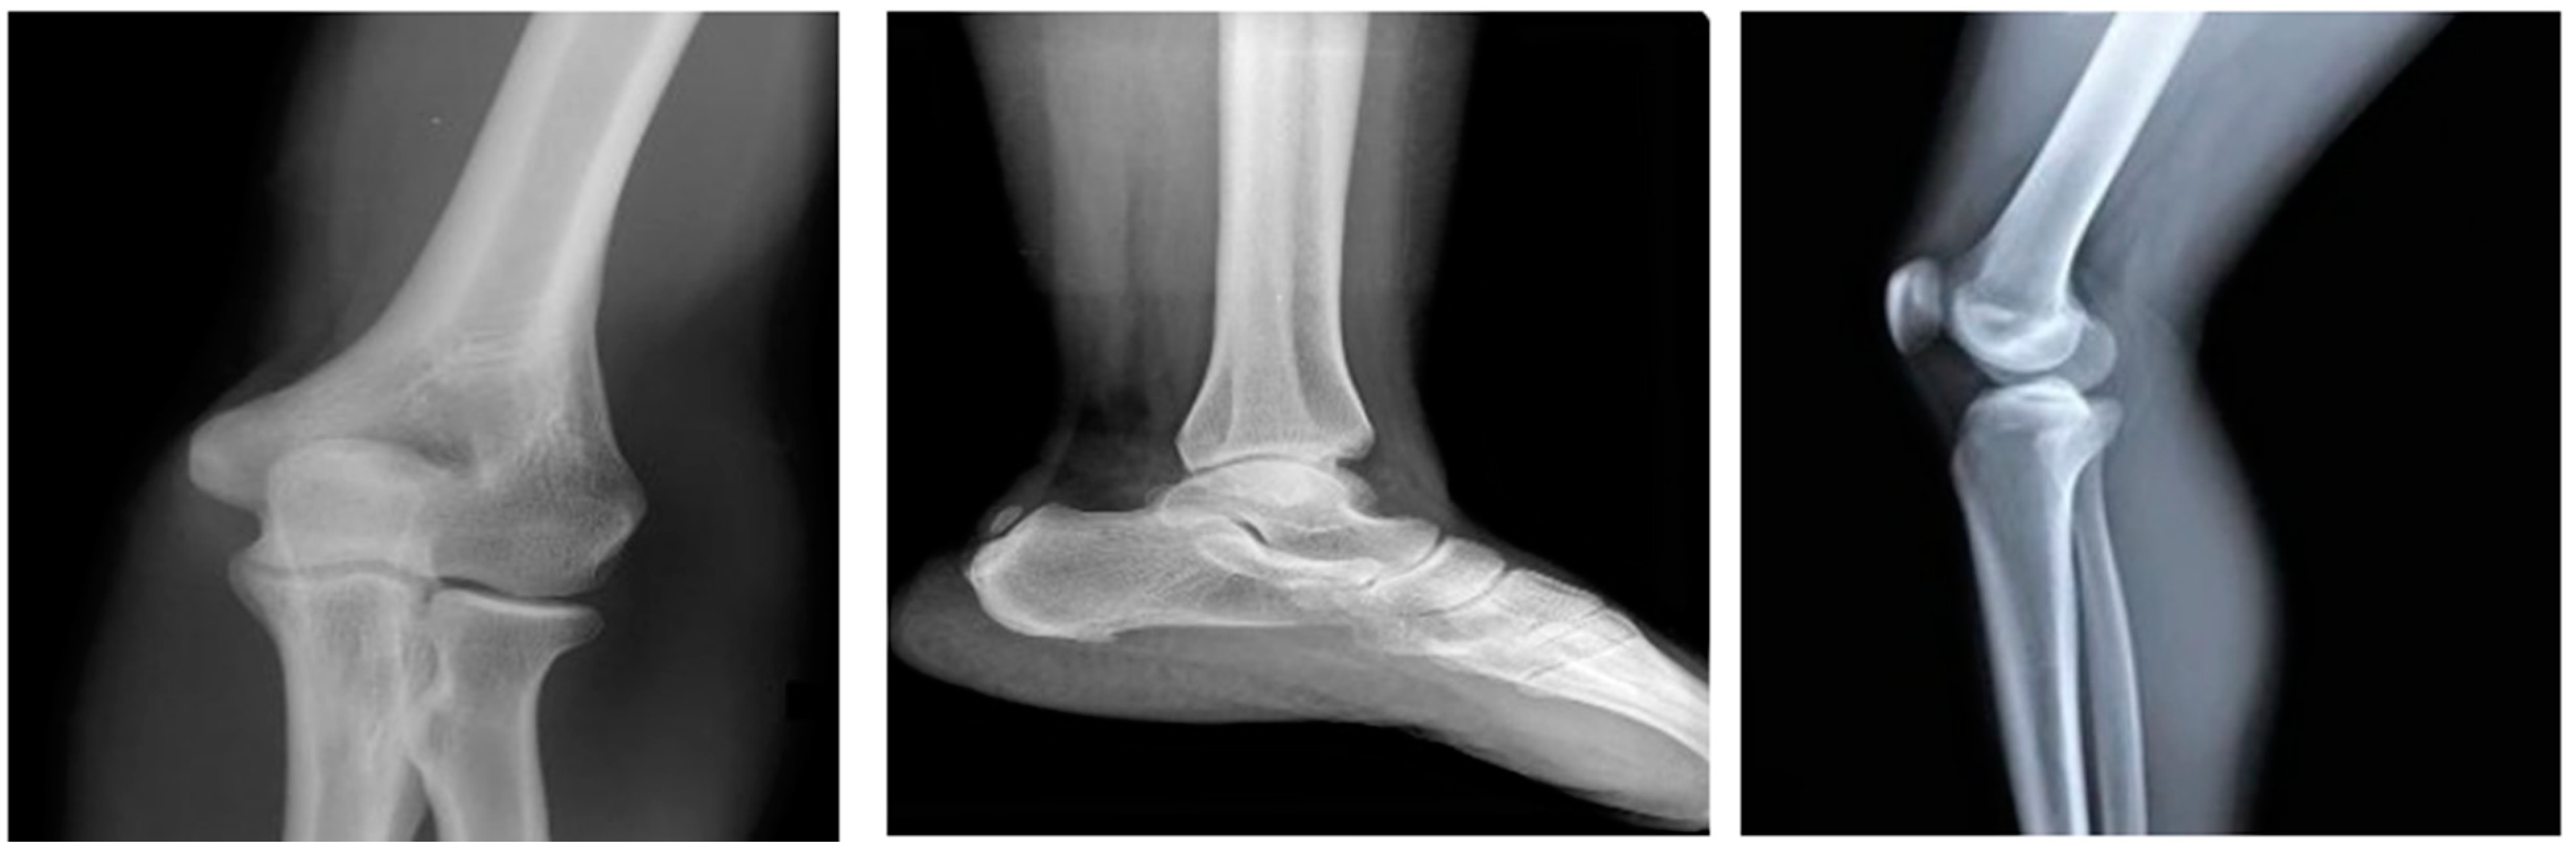

4.2. Results for Pre-Processing